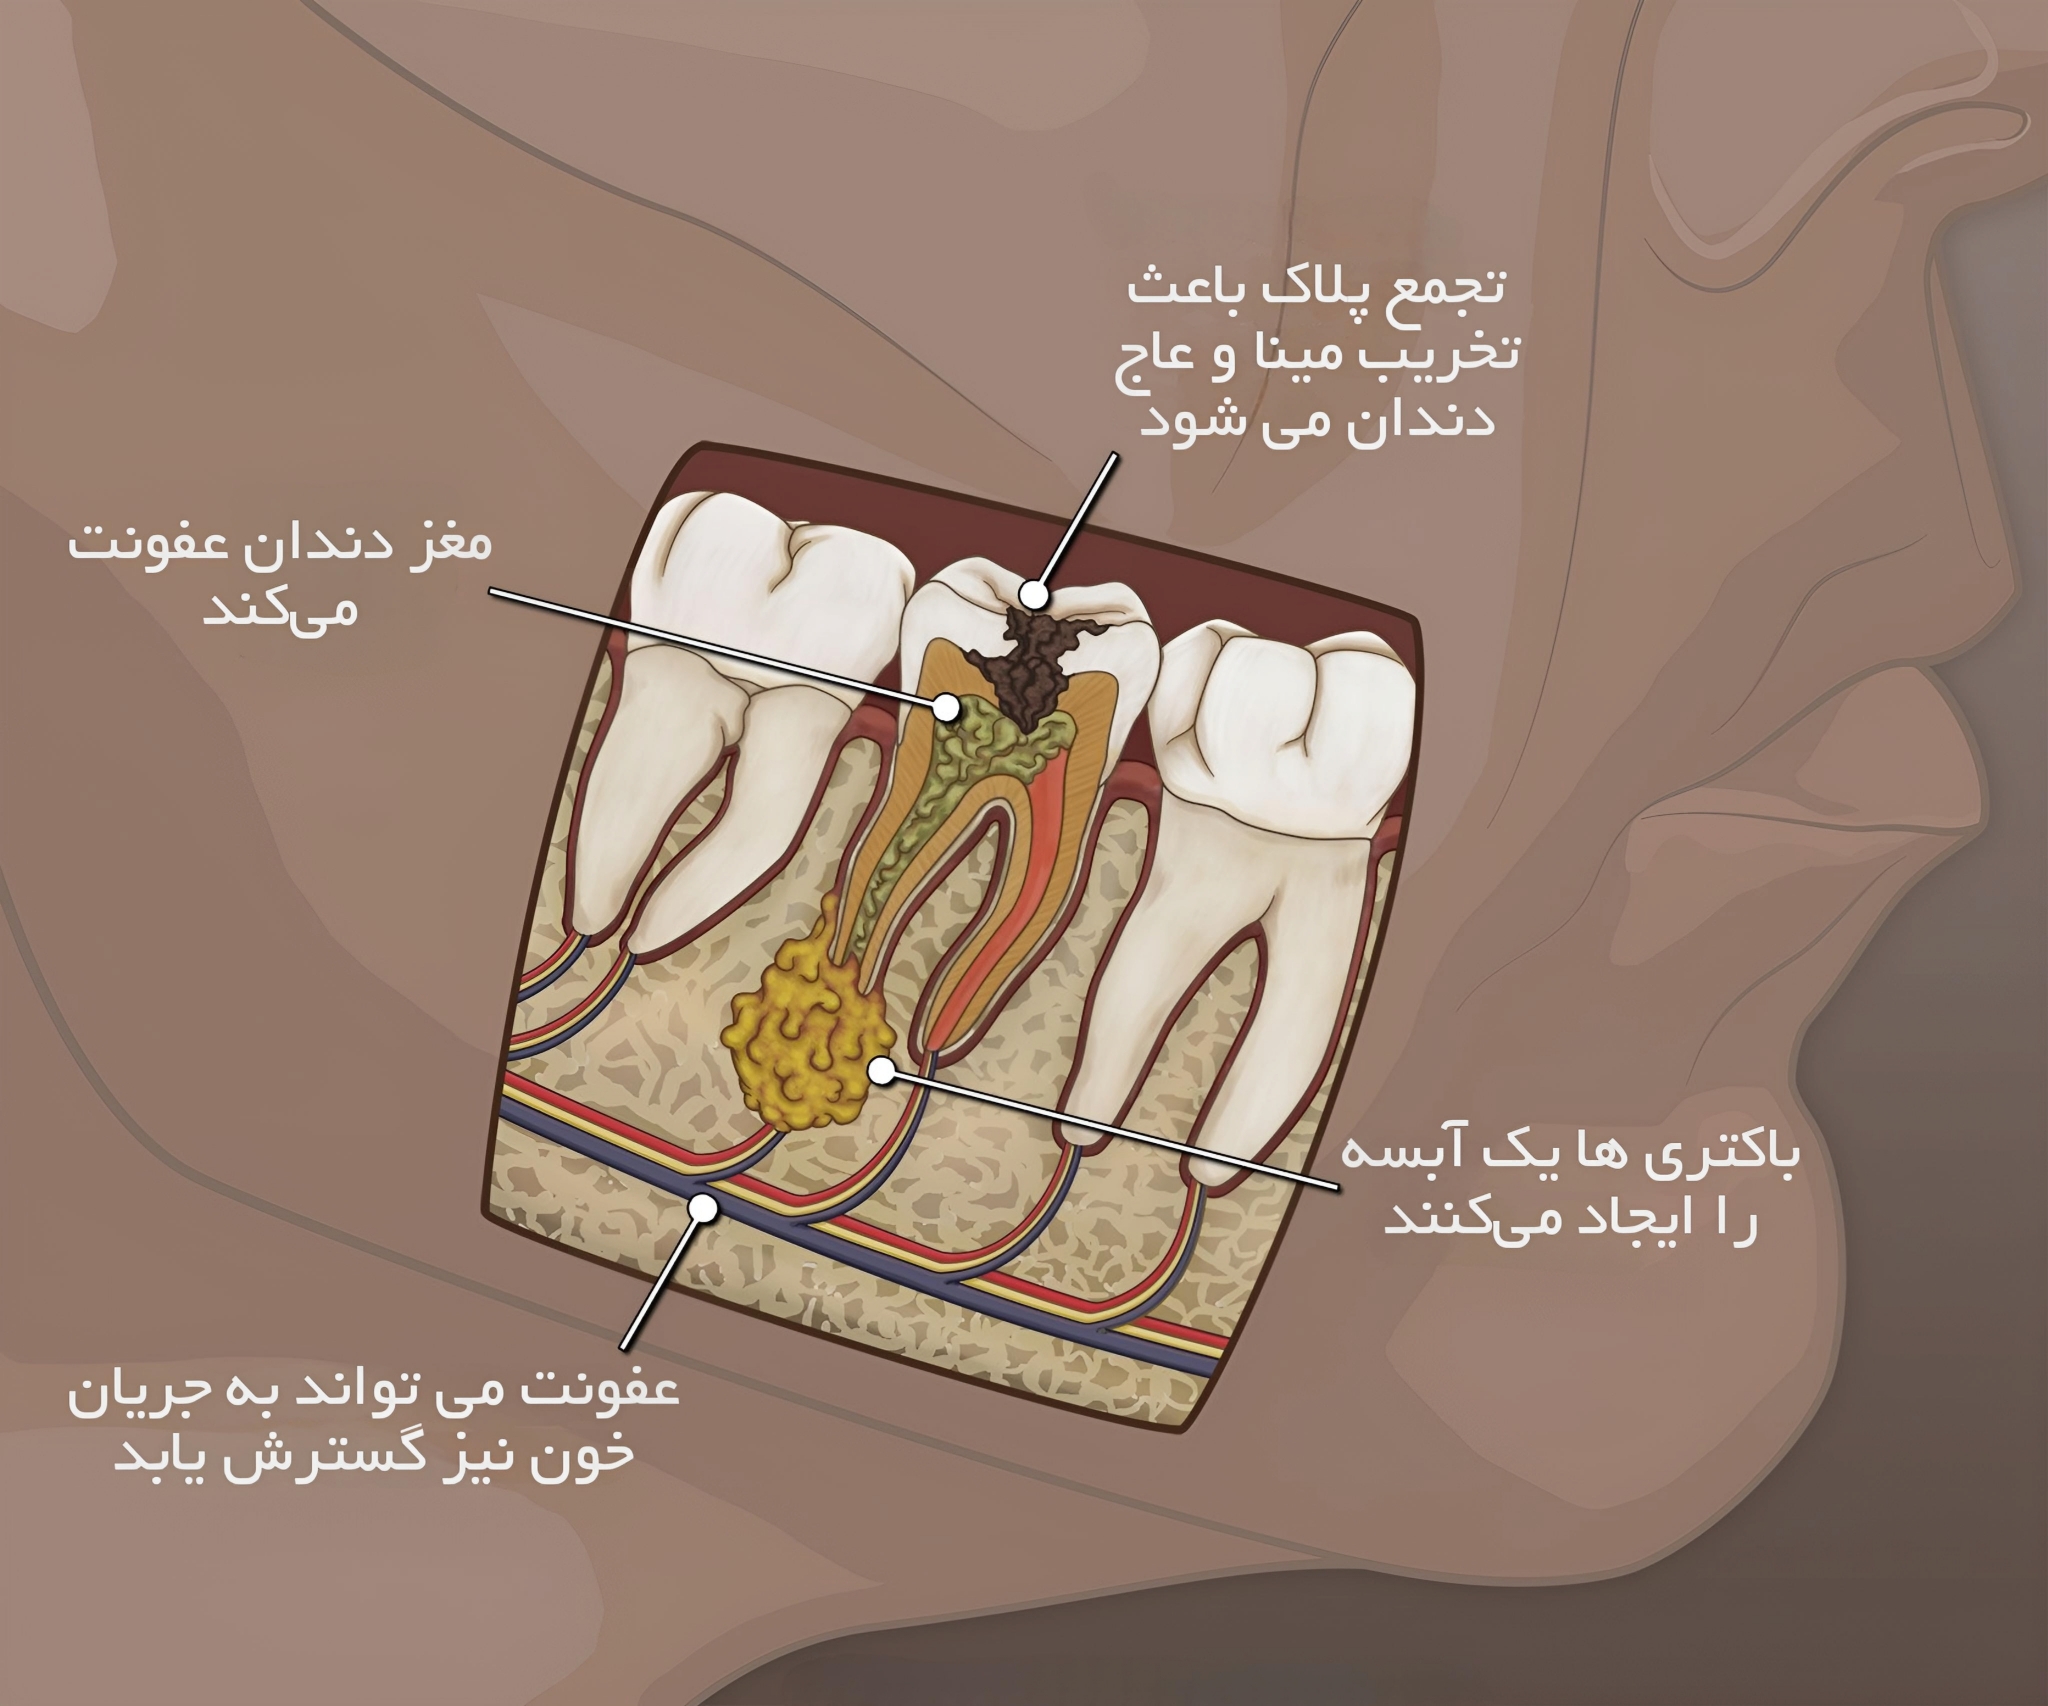

حال که با مفهوم پالپ آشنا شدید به ادامه بحث اصلی یعنی اینکه “چه زمان احتیاج به درمان ریشه دندان است” می پردازیم. درمان ریشه دندان زمانی نیاز است که مشخص شود بافت نرم مرکز دندان یا همان پالپ عفونی شده باشد. در این حالت دندانپزشک وضعیت دندان های شما را بررسی می کند و با عکس رادیولوژی وجود عفونت باکتریایی مشخص می شود. در عکس برداری رادیولوژی از پرتو ایکس (X) برای عکس برداری کردن از دندان خراب بیمار استفاده می شود. عفونت پالپ معمولاً در نتیجه پوسیدگی دندان ایجاد می شود.

عوامل زیادی وجود دارد که باعث آسیب زدن به پالپ میگردند که مهم ترین عامل آسیب زدن به پالپ دندان تأخیر در ترمیم پوسیدگی ها است که باعث نفود میکروب ها به پالپ دندان می شوند. پوسیدگی های دندانی اگر در مراحل ابتدایی درمان نشوند، بعد از تخریب مینا و عاج به پالپ رسیده و سبب التهاب، آماس و بیماری پالپ می شوند. عوامل دیگری که در آسیب دیدن پالپ نقش دارند عبارت است از: